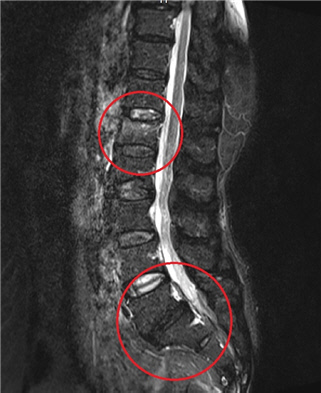

MRI 정밀검사 결과 급성 압박골절과 퇴행성 전방전위증이 관찰됐다. 척추는 척추뼈, 인대, 근육이 서로 단단하게 붙잡아 흔들리지 않아야 하는데, 나이가 들면 이 모든 것들이 약해지면서 척추가 흔들린다. 이러한 상태를 척추불안증이라 한다. 이 환자의 경우 오래 전에 발생한 척추불안증을 방치해 척추뼈가 앞으로 밀려 어긋나는 전방전위증으로 진행한 것으로 판단됐다.

환자와 보호자에게 사진을 보여드리며 압박골절과 전방전위증을 같이 치료하는 것이 좋겠다고 설명드렸다. 수년간 다리 통증이 심했던 터라 흔쾌히 치료에 동의하셔서 압박골절에 대한 시멘트 시술과 전방전위증에 대한 척추 고정술을 시행했다. 퇴원하고 2주 후에 통원치료를 받으러 내원했는데, “다리가 저리지 않는 이런 세상이 있었네”라며 하며 기뻐하셨던 모습이 기억난다.